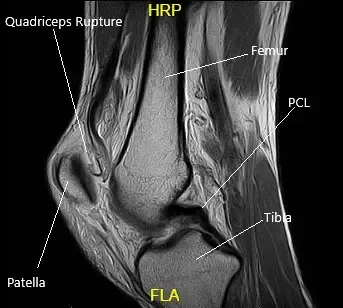

MRI suggested a complete rupture of the quadriceps tendon at the patellar attachment. The joint effusion communicates through the tendon defect with a prepatellar fluid collection. Low-grade intrasubstance tear at the origin of the ACL. Radial tear at the free edge of the lateral meniscal body.

MRI of the left knee in the sagittal and coronal view.

MRI of the Left Knee in the sagittal section.